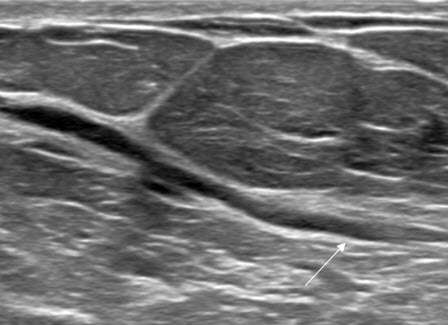

Ultrasound features include:

- Intraductal papillomas often appear as well defined solid intraductal masses within dilated ducts. They can exhibit a "frond-like" appearance projecting into the ductal lumen.

- Intraductal papillomas often demonstrate internal vascularity on color Doppler imaging. Furthermore, a vascular stalk may also be seen connecting to the ductal wall.